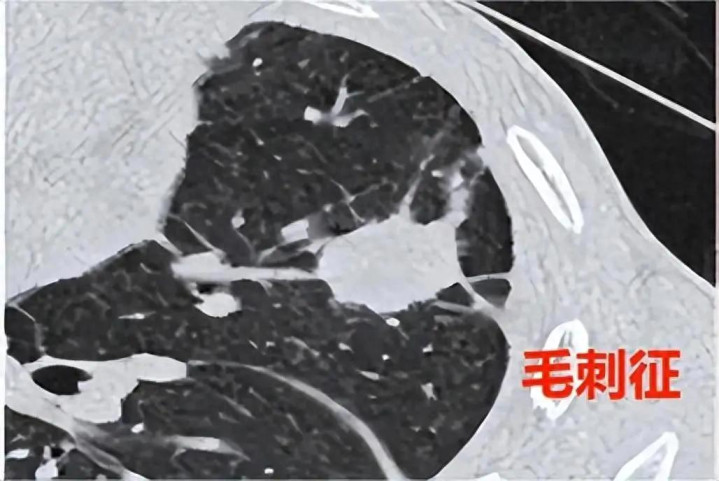

在CT报告单上,如果看到“毛刺征”三个字,很多肺结节朋友的心都会揪起来。影像上,它表现为从结节边缘向外放射的细小短线条,犹如太阳的光芒或刺猬的尖刺。西医认为,这常意味着肿瘤细胞向周围组织的浸润性生长,是提示恶性风险的一个重要形态学特征。

经三个月调理,复查CT显示:结节缩小至5mm,更重要的是原先的“多发短毛刺”已基本消失,边缘变光滑。这标志着结节活性受控,生长态势被成功逆转。患者大喜,信心倍增,后续加大散结力度,至再次复查时,已彻底消散!